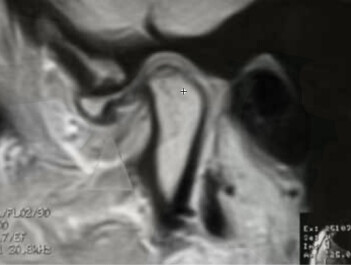

Die Magnetresonanz Tomographie dient vor allem der Darstellung von Weichgewebestrukturen.

Unter Umständen ist diese Darstellungsweise zum Beispiel bei Kiefergelenksbeschwerden oder bei Verdacht auf Speicheldrüsentumore notwendig und wird in einem auswärtigen Röntgeninstitut durchgeführt.